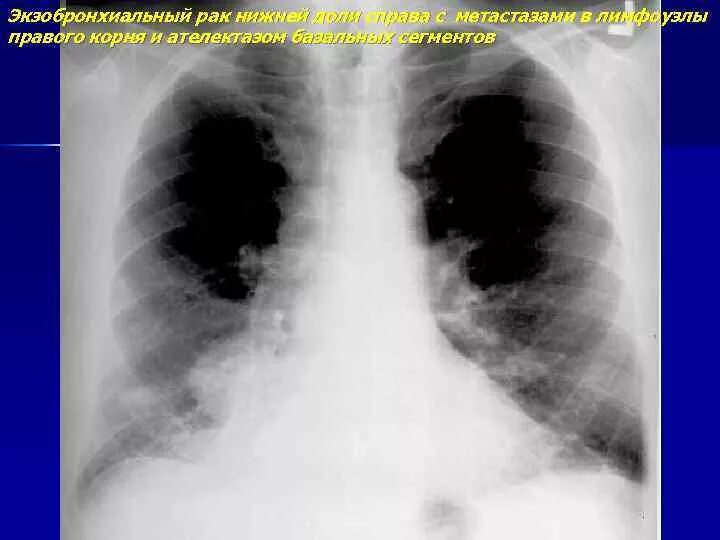

Метастазы в легких прогноз 4 стадия